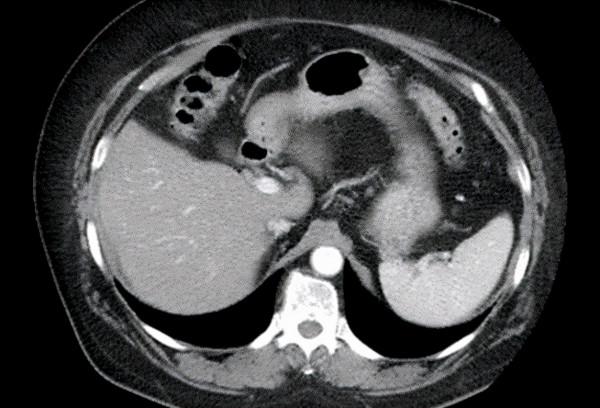

60歲女性前來接受新的患者評估,自述一年前失去丈夫後一直患有抑鬱症,每天喝大約60g酒。最近在急診室就診期間接受了腹部CT掃描(如圖3)。

在回顧CT 掃描時,考慮哪些變化是繼發於酒精,包括酒精性肝脂肪變性、酒精性肝炎、酒精性肝硬化、肝細胞癌。答案是酒精性肝脂肪變性。每天攝入超過60g酒精會導致肝臟的形態變化,出現肝臟的脂肪替代或肝脂肪變性。酒精性脂肪肝被認為是由於脂肪酸和甘油3-磷酸鹽的增加.較新的成像技術,如雙能CT,顯示出量化脂肪變性程度的潛力。肝脂肪變性是可逆的,但如果攝入酒精沒有減少,就會發生酒精性肝炎,隨後是酒精性肝硬化。